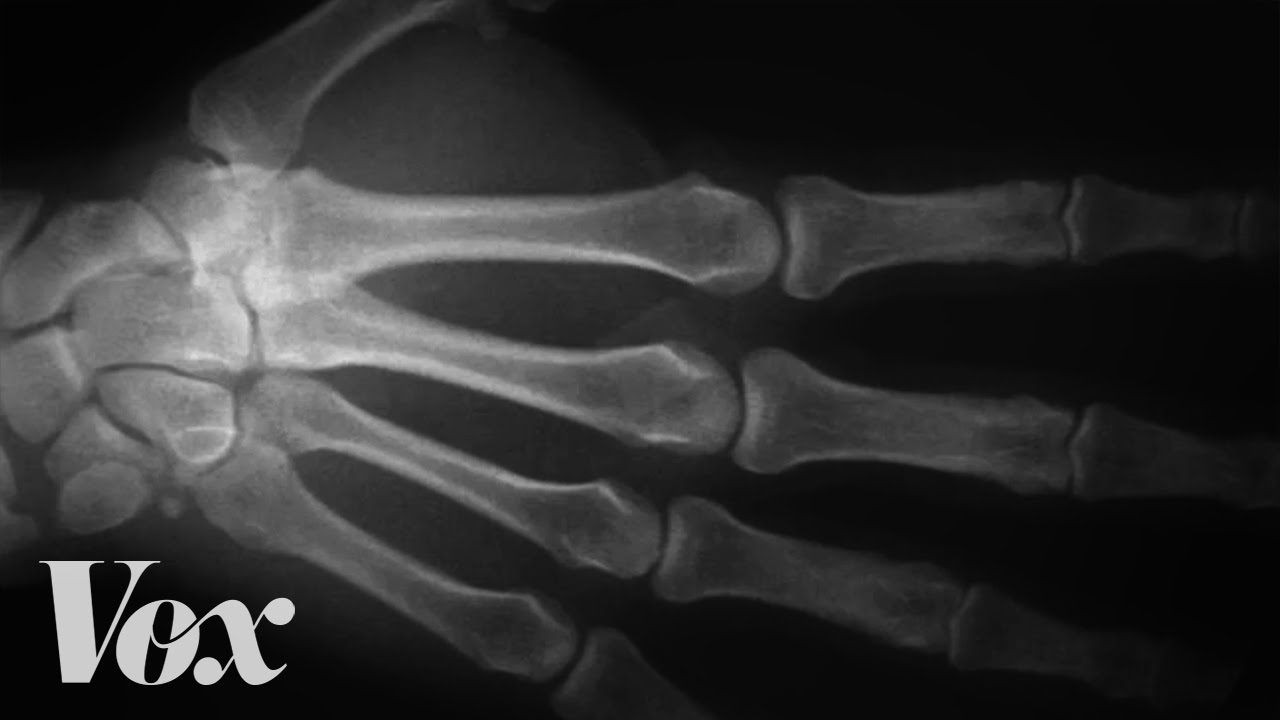

But the most common explanation for why your stretched-out joints sound like bubbles popping is that, well, there are bubbles in there. The joints in your fingers are the easiest ones to crack, but many people also crack the joints between vertebrae in their neck and back, and even their hips, wrists, shoulders and so on. All these joints are synovial joints, and they're the most flexible ones in your body.

The space between the two bones is filled with a viscous liquid, synovial fluid, which contains long, lubricating molecules, like hyaluronic acid and lubricin. Synovial fluid is more or less the texture of egg yolk and its primary purpose is to cushion the bones and help them glide past each other. It also contains phagocytic cells that help clean up any bone or cartilage debris that ends up in the joint.

But the reason it's important for knuckle cracking is that, like other fluids in your body, it contains lots of dissolved gas molecules. Knuckle-crackers know that to get that satisfying pop, you stretch the joint farther than it normally goes by bending your fingers backwards, for example. When you do that, the bones move away from each other.

The space between bones gets bigger, but the amount of synovial fluid stays constant. That creates a low-pressure zone that pulls dissolved gases out of the synovial fluid, just like the carbon dioxide that fizzes out of soda when you twist open the cap. Inside the joint, the escaping gases form a bubble with a pop.